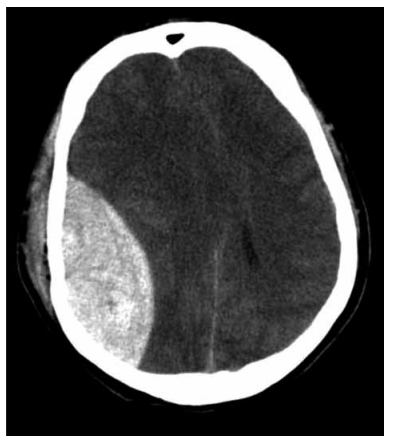

Homem de 39 anos dá entrada no pronto-socorro de um hospital após queda de escada (altura aproximada de 2,5 m). Apresenta afundamento de crânio em região parietal direita com sangramento ativo. Exame neurológico: AO = ao estímulo doloroso; RV = emitiu sons incompreensíveis; RM = flexão anormal; otorragia ipsilateral e anisocoria. Estável hemodinamicamente. Realizado atendimento inicial corretamente e como não há neurocirurgião na unidade, o paciente será transferido a um hospital de referência em Trauma. Tomografia de crânio demonstrada a seguir.

Assinale a alternativa que contempla, respectivamente, o correto escore da Escala de Coma de Glasgow (ECG), o diagnóstico da lesão e a terapia medicamentosa indicada para redução inicial da pressão intracraniana.